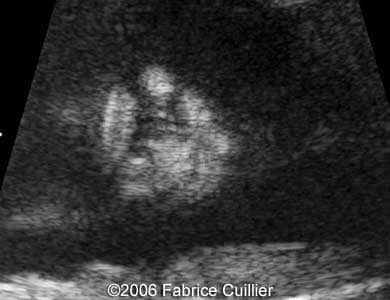

Pictures 3, 4. 2D and 3D pictures showing unilateral cleft lip.

Pictures 5, 6. 3D pictures showing unilateral cleft lip.